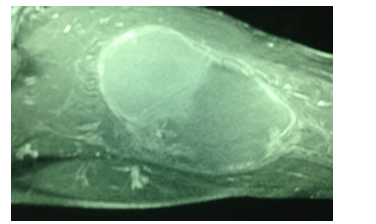

A imagem a seguir, de uma RNM da coxa direita, representa uma massa de crescimento rápido no grupo muscular posterior de um paciente do sexo masculino, negro, com lesões umbilicadas em tronco e membros superiores e inferiores. Chama a atenção a presença de uma mancha do tipo “café com leite”no ombro esquerdo. A biópsia incisional dessa lesão revelou “neoplasia fusiforme de padrão sarcomatóide; provavelmente se trata de um rabdomiossarcoma“.

A respeito desse caso clínico e da doença genética que predispõe ao surgimento da neoplasia, julgue os itens a seguir.

A mutação do gene NF1 – neurofibromatose congênita tipo 1 – está associada ao quadro clínico apresentado. Uma mutação autossômica dominante localizada no gene 17q11.2 também se relaciona aos gliomas ópticos e aos nódulos de Lisch na íris.

A mutação do gene p53 – síndrome de Li-Fraumeni – origina esse tipo de doença pela perda da atividade regulatória da proteina codificada pelo gene p53 no ciclo celular.